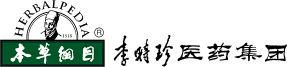

“传时珍医药伟业,谱本草科学新篇”,医药集团致力为广大用户提供一系列高质量的产品,涵盖了中成药、中药饮片、中药配方颗粒、保健酒、蕲艾系列大健康产品生产以及子公司厦门美商医药的化药。我们的产品结合了传统中医药炮制与现代科学技术,为用户提供健康、安全和有效的医药保健解决方案。 医药集团主要生产中成药品种近100个,其中40余个基药品种可纳入医保目录。此外,集团还生产中药配方颗粒品种350余个,中药饮片品种700余个,以及蕲艾制品100余个。这些产品经过多次的GMP认证,保证其质量和安全性。